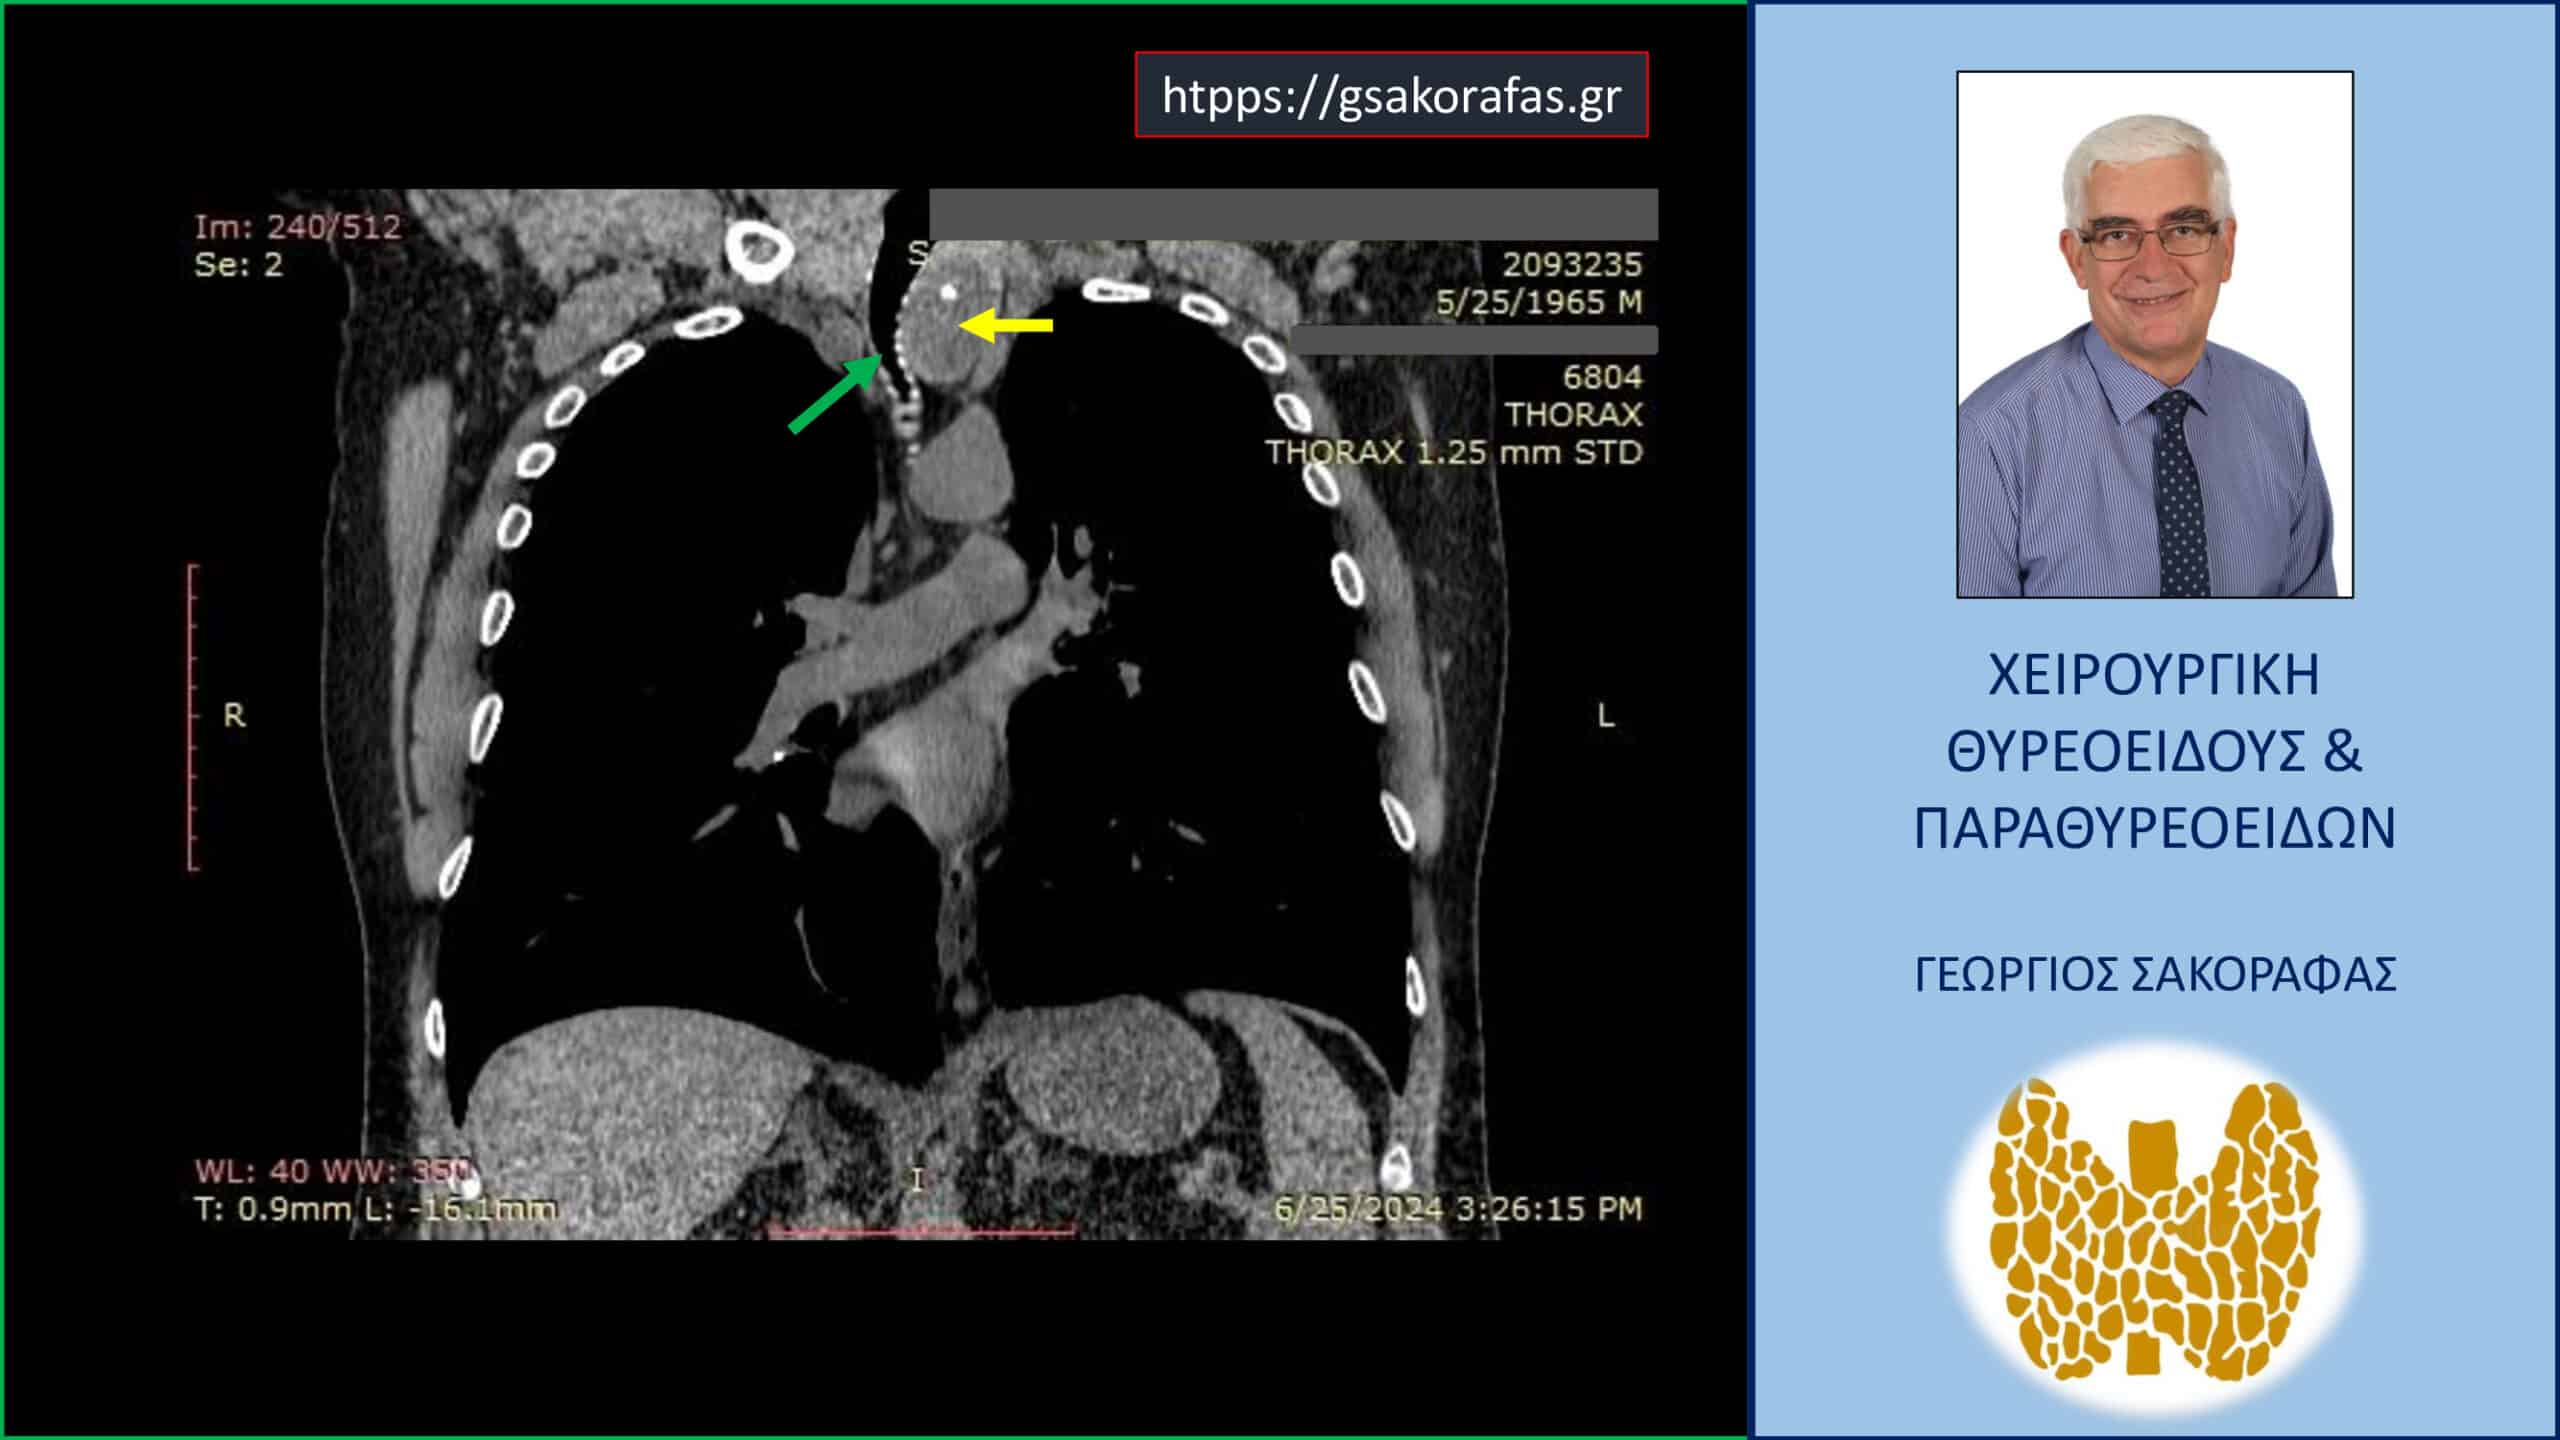

Ευμεγέθης καταδυόμενη βρογχοκήλη – απεικόνιση στην αξονική τομογραφία (σε κατά μέτωπο διατομή). Ο καταδυόμενος αριστερός λοβός του θυρεοειδούς (κίτρινο βέλος) φθάνει εγγύς στο αορτικό τόξο και απωθεί την τραχεία προς τα δεξιά (πράσινο βέλος) προκαλώντας στένωση του αυλού της.

Για την αξιολόγηση του βάθους κατάδυσης του θυρεοειδούς στο μεσοθωράκιο ο ασθενής υποβλήθηκε σε αξονική τομογραφία όπου ο αριστερός λοβός απεικονίζεται σε θέση κατάδυσης μεταξύ της έκφυσης της αριστερής κοινής καρωτίδας και της ανωνύμου αρτηρίας φτάνοντας εγγύς του άνω ορίου του αορτικού τόξου. Ασθενής ευθυρεοειδικός.